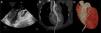

A 27-year-old woman was admitted to our center after emergency vascular surgery for spontaneous dissection of the left iliac artery. Congenital factor VIII deficiency and family history of complicated brain aneurysm were previously reported. Hemoperitoneum and hemothorax were identified after surgery as consequences of a severe coagulation disorder and the patient suffered cardiac arrest with pulseless electrical activity. A portable echocardiograph detected pericardial effusion and emergency blind subxiphoid pericardiocentesis was performed with recovery of pulse. An urgent cardiology evaluation was subsequently required. Transthoracic echocardiography views were severely limited, so it was decided to undertake transesophageal echocardiography. This revealed a catheter crossing the aortic valve to the ascending aorta (Figure 1A). Contrast-enhanced computed tomography angiography confirmed the intravascular placement of a drainage with its distal tip in the proximal segment of the left carotid artery (Figure 1B). The ventricular insertion point was in the anterior interventricular groove, close to the distal segment of the left anterior descending coronary artery (Figure 1C). Prior to entering the operating room, the patient suffered a new cardiac arrest and resuscitation maneuvers were ineffective. Subsequent autopsy revealed systemic vascular and tissue fragility (spontaneous liver and spleen lacerations, aortic rupture and hyoid bone fracture with minimal procedural manipulation), compatible with a diagnosis of type 4 Ehlers-Danlos syndrome.

Multimodality imaging of the path of the pericardiocentesis catheter crossing the aortic valve to the ascending aorta. (A) Two-dimensional transesophageal echocardiogram, left ventricular outflow tract projection; (B) computed tomography curved format reconstruction along the catheter; (C) three-dimensional volume-rendered computed tomography reconstruction of the catheter insertion point and its relationship with the anterior descending artery.